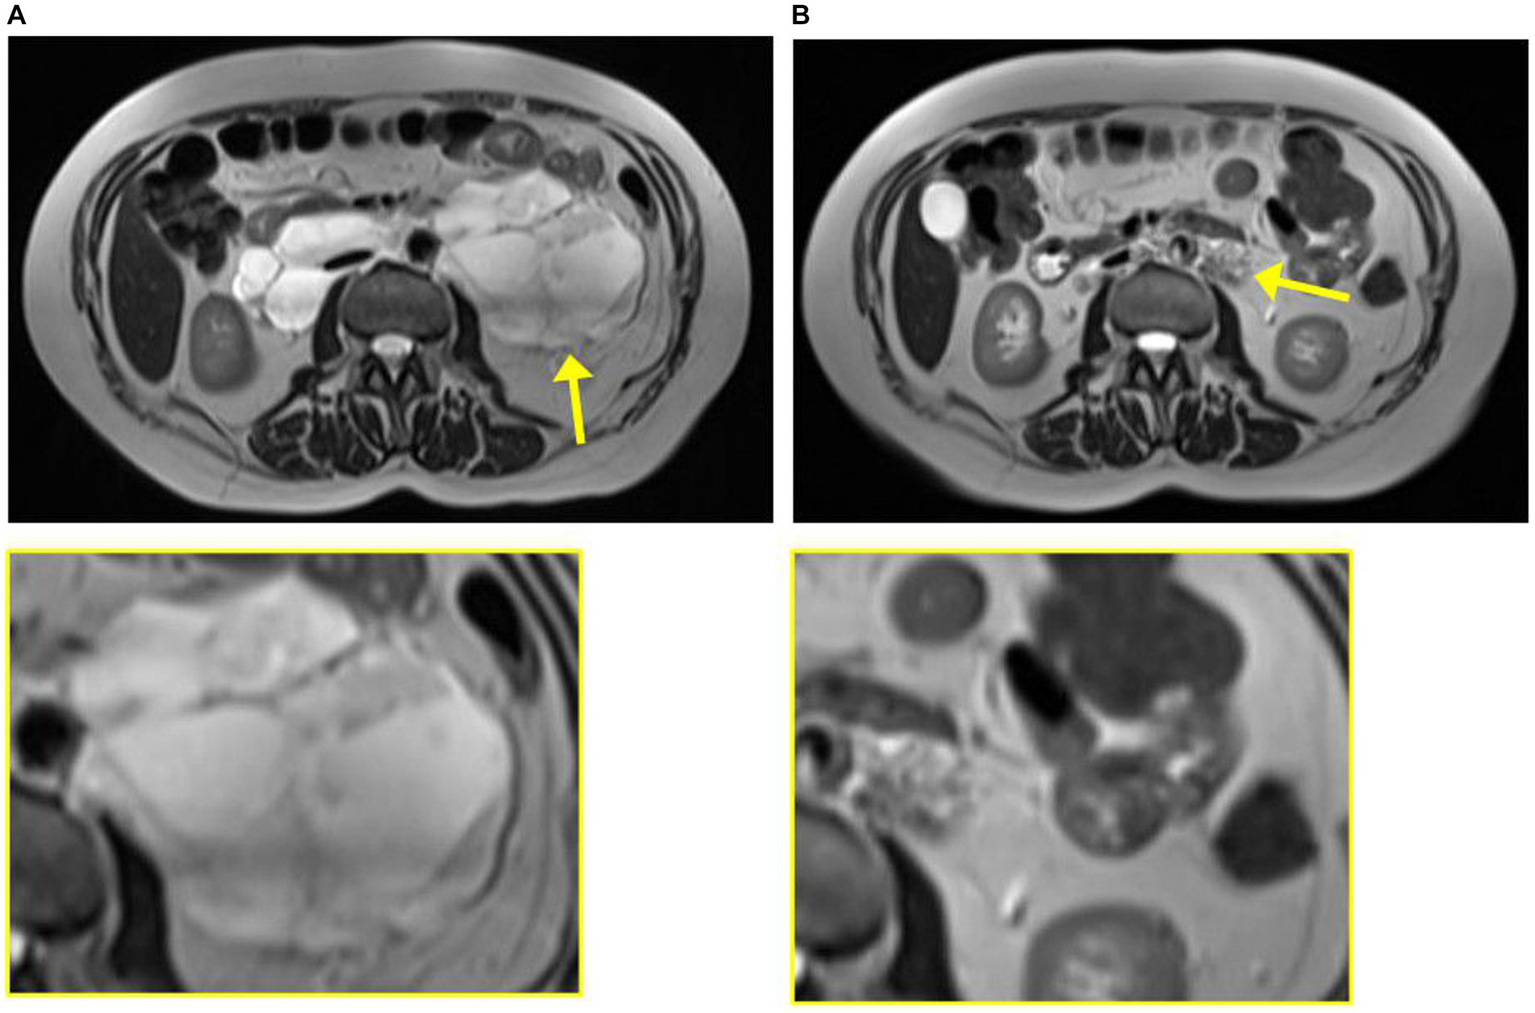

Figure 2

Magnetic resonance imaging from case 1 from 2020 at diagnosis of leiomyoma (A) and 2023 at diagnosis of lymphangioleiomyomatosis (B). The tumor is indicated by the yellow arrow and enlarged in the yellow box.

The patient was regularly followed with an MRI, showing regression of the tumor (Figure 2). Each time, the scans were evaluated at a highly specialized gastrointestinal multidisciplinary conference, attended by oncologists, pathologists, gastrointestinal surgeons, and radiologists. Due to the infiltration of the large blood vessels, curative surgery was not an option. Clinically, she was experiencing increased abdominal pain despite tumor regression. For a period of 3 months in 2021, the treatment with pazopanib was put on pause, which resulted in tumor progression. Therefore, the treatment was resumed.